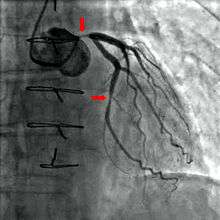

Coronary catheterization is one of the several cardiology diagnostic tests and procedures. Specifically, coronary catheterization is a visually interpreted test performed to recognize occlusion, stenosis, restenosis, thrombosis or aneurysmal enlargement of the coronary artery lumens; heart chamber size; heart muscle contraction performance; and some aspects of heart valve function. Important internal heart and lung blood pressures, not measurable from outside the body, can be accurately measured during the test. The relevant problems that the test deals with most commonly occur as a result of advanced atherosclerosis – atheroma activity within the wall of the coronary arteries. Less frequently, valvular, heart muscle, or arrhythmia issues are the primary focus of the test.

If atheroma, or clots, are protruding into the lumen, producing narrowing, the narrowing may be seen instead as increased haziness within the X-ray shadow images of the blood/dye column within that portion of the artery; this is as compared to adjacent, presumed healthier, less stenotic areas. See the single frame illustration of a coronary angiogram image on the angioplasty page.